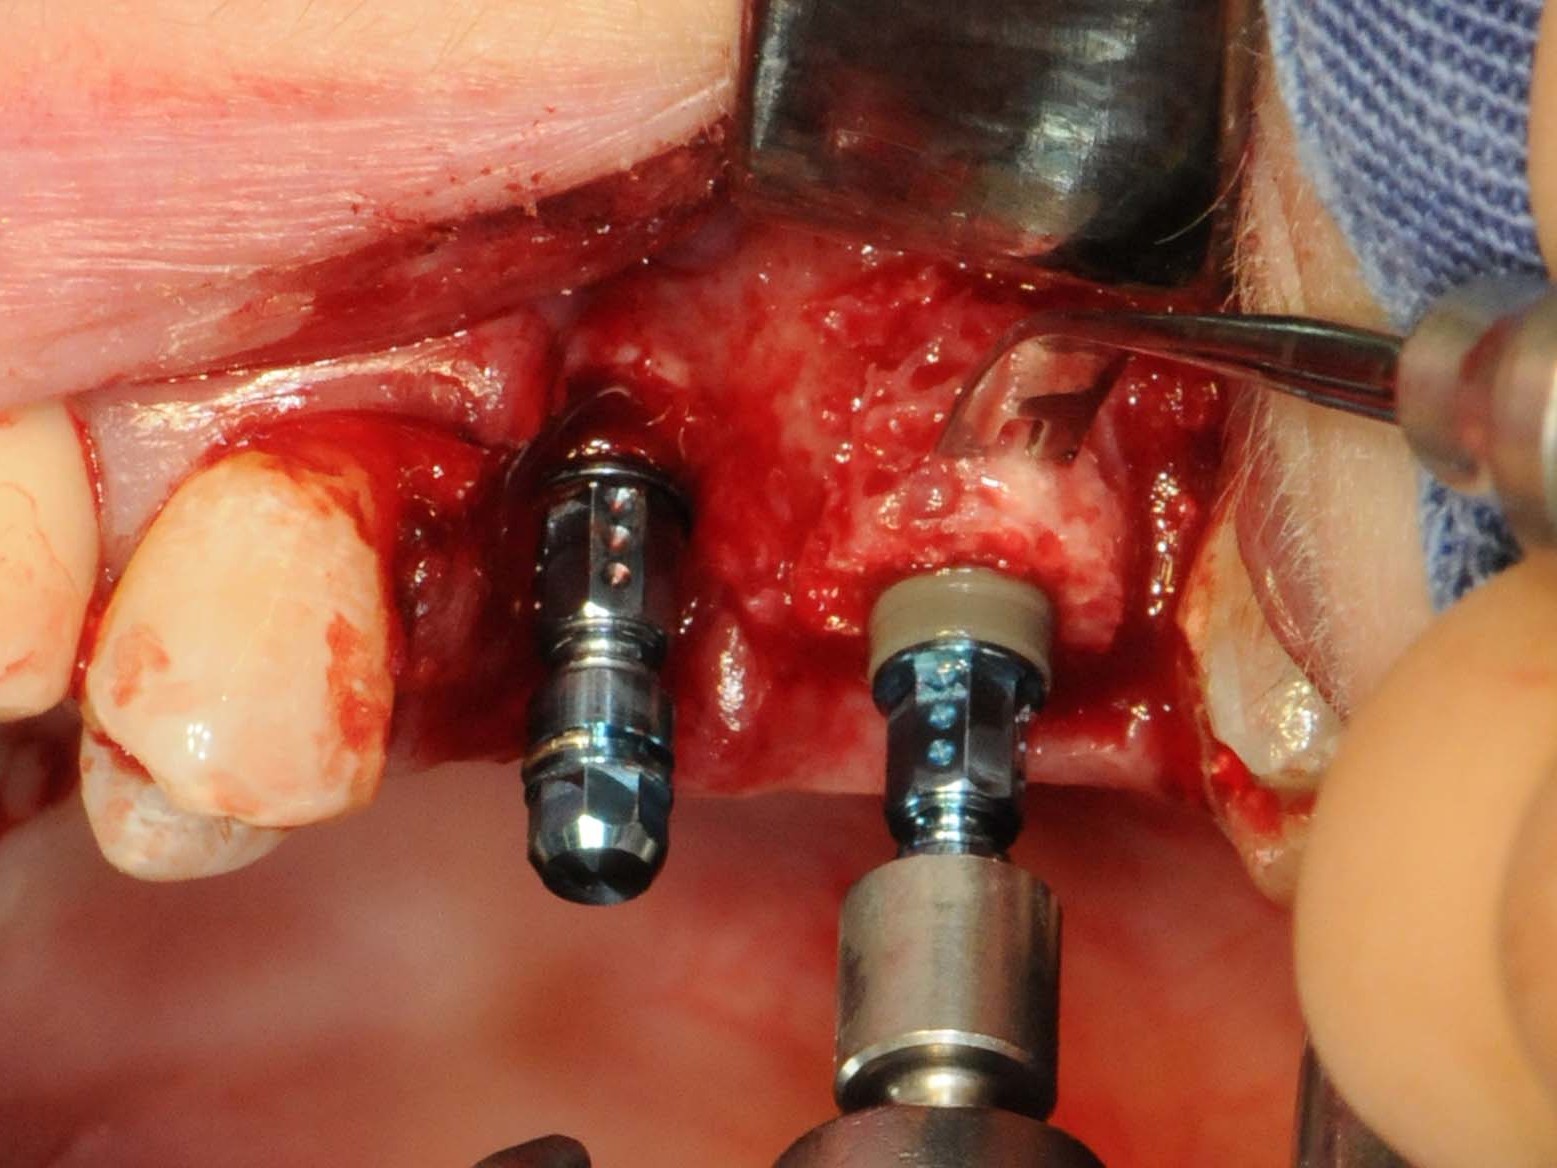

Abb 13 Straumann Bone Level Roxolid-Implantat als Sofortimplantation eingesetzt

Abb. 13: Straumann Bone Level Roxolid-Implantat als Sofortimplantation eingesetzt

Abb 14 Straumann Bone Level Roxolid-Implantat 25 in finaler Position

Abb. 14: Straumann Bone Level Roxolid-Implantat 25 in finaler Position

Unter oraler Antibiose mittels Clindamycin 600mg 2 x/Tag erfolgte zunächst die typische minimalinvasive Präparation des Mukoperiostlappens unter Erhalt der Papillen zu den Nachbarzähnen in Regio 12 (Abb. 6), nachdem die Brücke von Zahn 11 nach 14 entfernt wurde (Abb. 7). Wegen Nichtanlage von 13 steht der Zahn 14 in dessen Region. Seinerzeit wurde der Zahn 14 zur Aufnahme einer entsprechenden Eckzahnkrone umgestaltet. Die Implantatbettpräparation (Abb. 8 und 9) für das Straumann PURE Ceramic Implantat (Ø 3,3 mm, Länge 12mm) erfolgte gemäß dem Straumann Guided Surgery Protokoll. Die abschließende Implantatinsertion wurde dem Protokoll für die Straumann PURE Ceramic Implantatlinie gemäß durchgeführt (Abb. 10 und 11). In der Implantatsetzungsregion des zweiten Quadranten wurde zunächst die Inlay-Brücke von Zahn 25 nach 27 entfernt. Seitens des zahntechnischen Labors wurde das Zahninlay von Zahn 27 von der Brücke getrennt und wieder inkorporiert. Nach der Extraktion des tief zerstörten Zahnes 25 erfolgte die typische Mukoperiostlappenpräparation. Nach Darstellung des Insertionssitus kam die massive vestibuläre Knochendefizitsituation in Regio 26 zur Darstellung (Abb. 12). Zunächst wurde die Präparation der Implantatstollen in Regio 25 und 26 gemäß dem Straumann Guided Surgery-Protokoll durchgeführt. In Regio 25 wurde ein Straumann Bone Level Roxolid Implantat (Ø 4,1 mm, Länge 12mm) als Sofortimplantation eingesetzt (Abb. 13 und 14). In Regio 26 wurde ein Knochenring CHB¹⁶ zur Augmentation des vestibulären Knochendefizits entsprechend des ossären Knochenabhanges angeschrägt und in der Höhe eingekürzt (Abb. 15). Die Anpassung des homologen Ringes erfolgt unter Fixierung mit der bonering fix-Zange und Anwendung einer 10-mm-Diamanttrennscheibe (Abb. 16).

Der Knochenring wurde entsprechend dem Bohrprotokoll für das 4,1-mm-Implantat extrakorporal mit dem passenden Einmalbohrer aufbereitet. Danach wurde das Straumann Bone Level Roxolid-Implantat (Ø 4,1 mm, Länge 8 mm) extrakorporal maschinell in den homologen Knochenring, der mit der bonering fix-Zange gehalten wurde, eingebracht (Abb. 17). Anschließend wurde das Implantat samt Knochenring in die Implantatbettregion der Mundhöhle verbracht und entsprechend subkrestal maschinell versenkt (Abb. 18). Nach Entfernung der Loxim-Einbringhilfe wurden beide Implantate mit Verschlussschrauben versehen. Der Resorptionsschutz erfolgte mittels synthetischem biphasischen Kalziumphosphat¹⁷ eine Abdeckung des Augmentats (Abb. 19). Zusätzlich fand eine Membran aus porcinem Perikard ihre Anwendung.¹⁸ Abschließend erfolgte der typische spannungsfreie Naht-Wund-Verschluss. In der Frontzahnregion wurde eine präoperativ gefräste PMMA-Kunststoffbrücke eingesetzt (Abb. 20), die im Bereich des Zwischengliedes eine belastungsfreie Einheilung des Straumann PURE Ceramic Implantat gewährleistet. Im Seitenzahnbereich verblieb die Zahnlücke auf Wunsch der Patientin unversorgt, da ein gaumenüberspannender Zahnersatz nicht toleriert wird. Das abschließende Orthopantomogramm zeigt die Implantat- und Augmentationssituation radiologisch (Abb. 21).